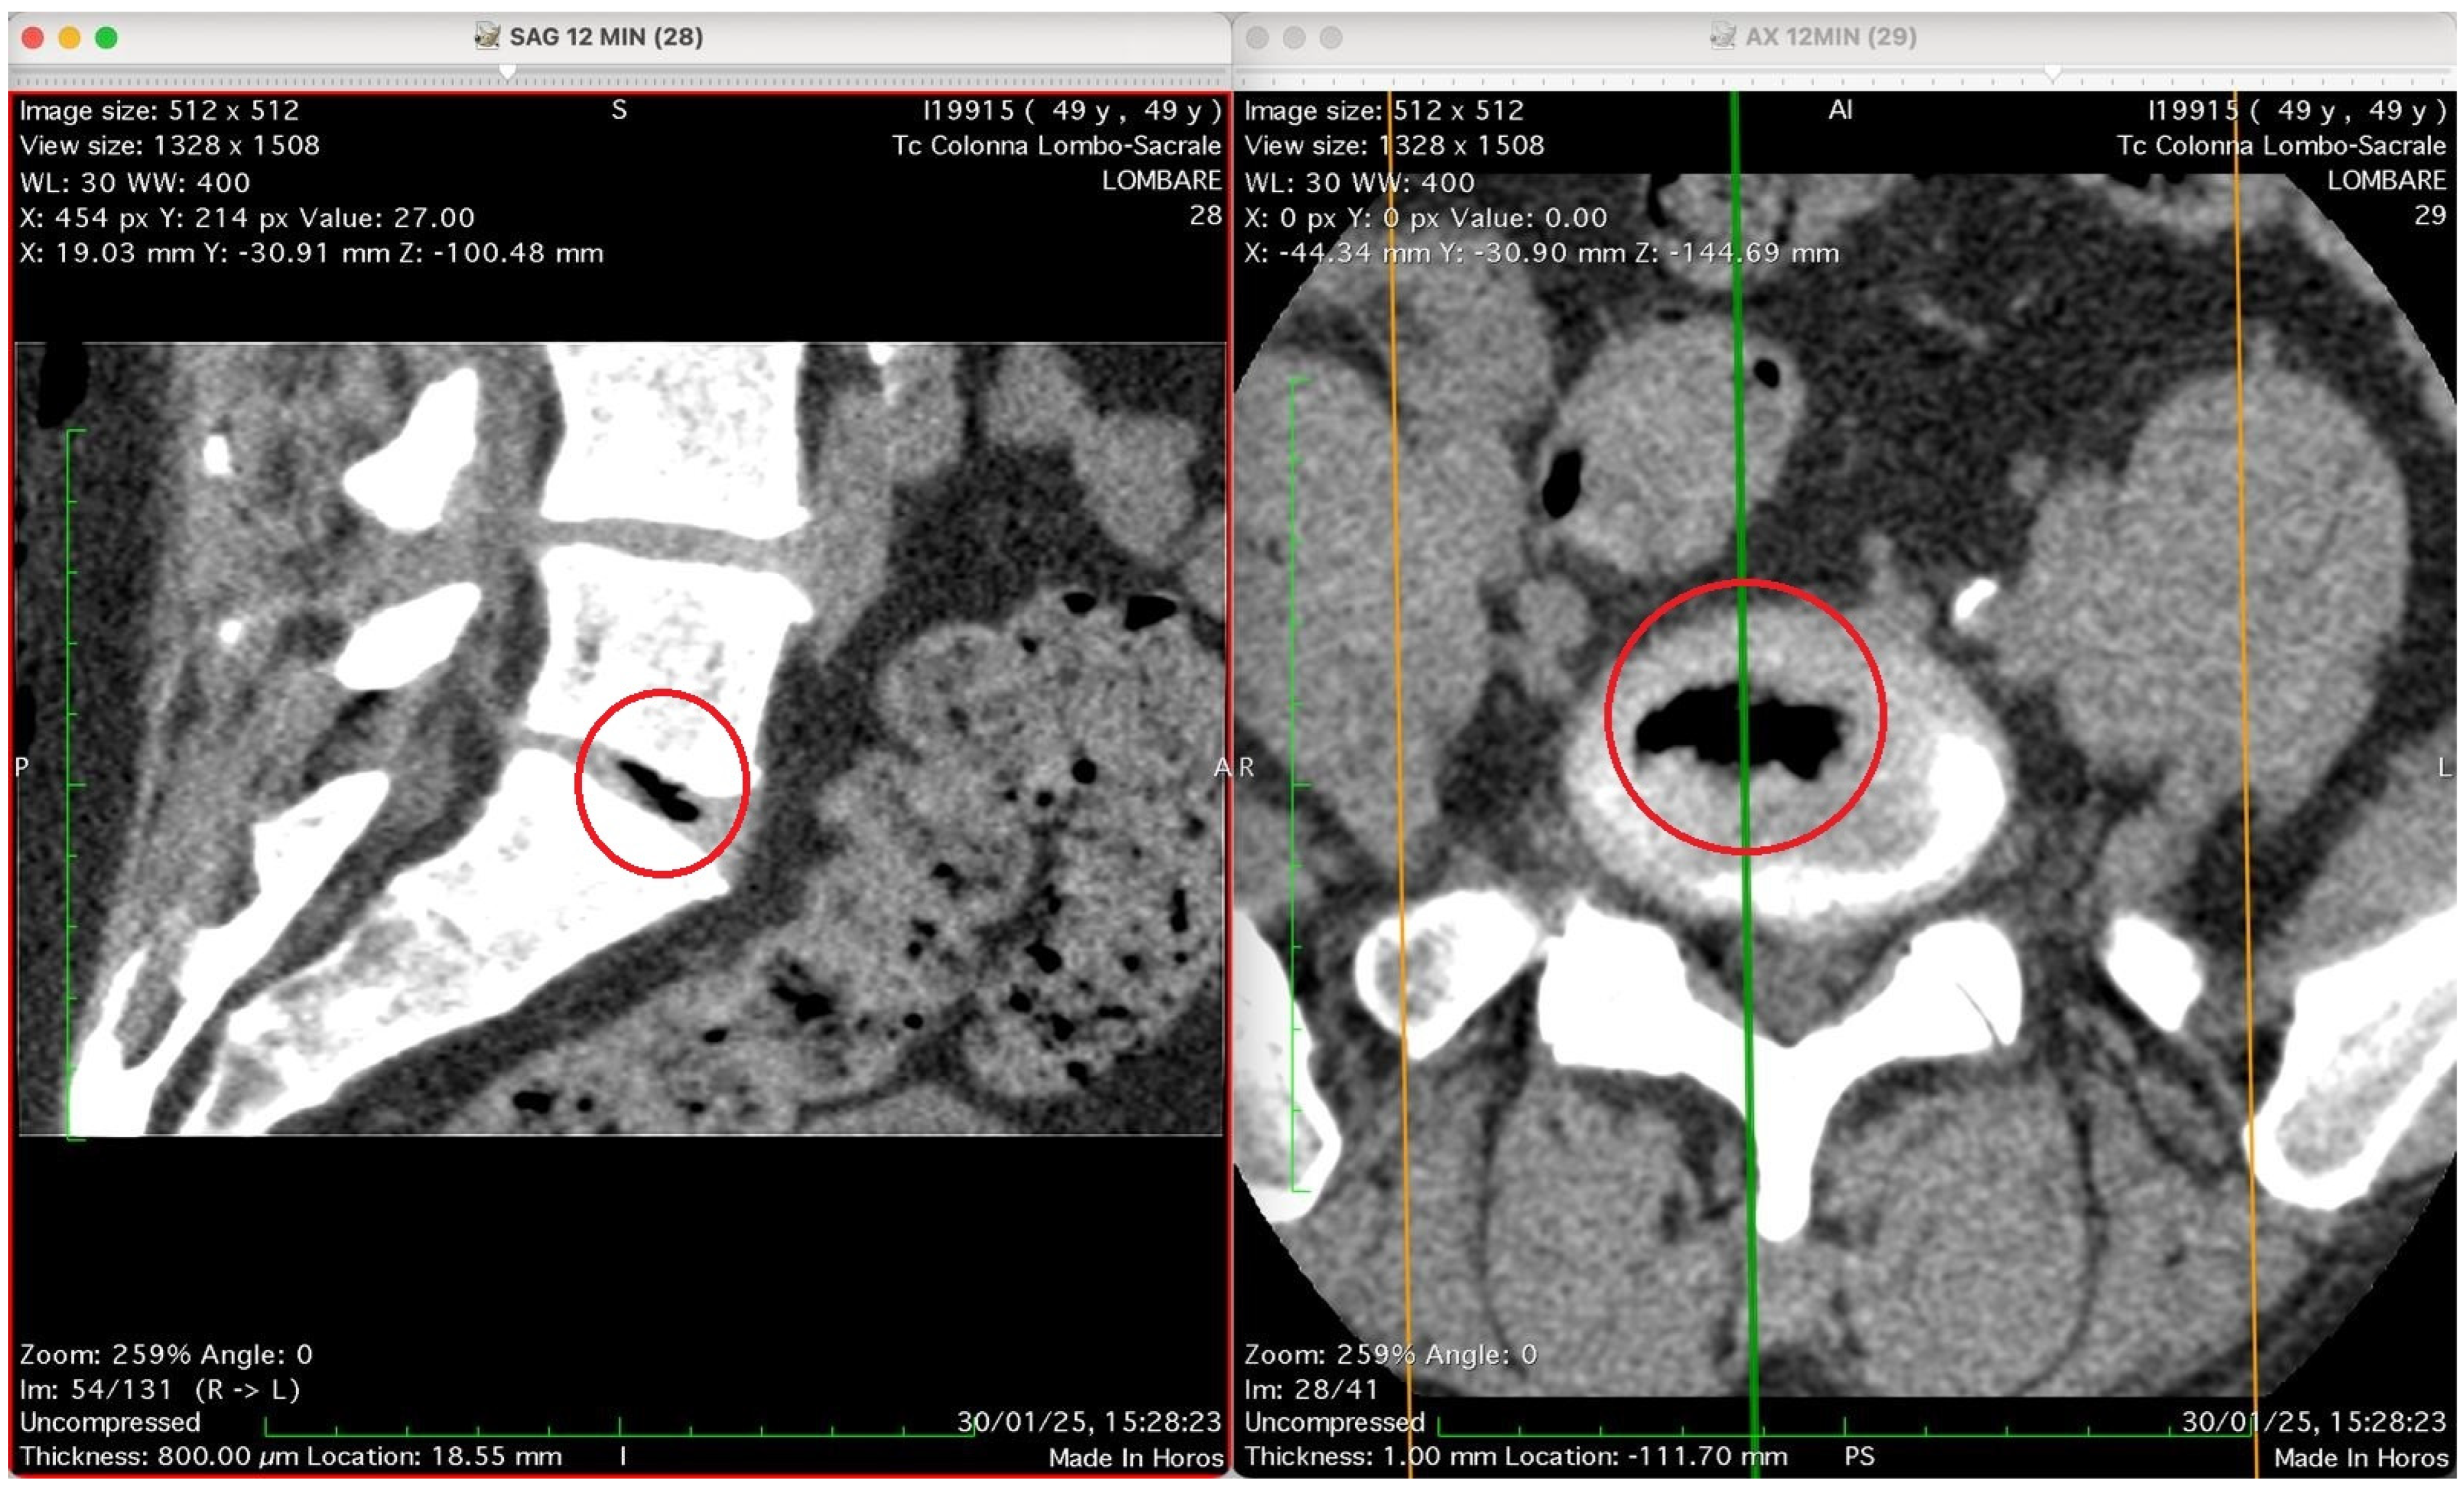

Figure 2, Figure 3, Figure 4 and Figure 5 show four computed tomography (CT) scans, along a time-course analysis, of the lumbosacral spine, visualized in sagittal (left) and axial (right) planes, from an exemplificative male patient (49 years) with L5-S1 herniated disc, undergoing an experimental setting of oxygen–ozone therapy via the intramuscular approach (Revolution™ CT, GE-Healthcare, Chicago, IL, USA). The very low-density ozone gas (hypodense, dark black within cred circles), spreads over the intervertebral disc within the time course of less than 10–20 min, assessing that ozone in the oxygen medium really reaches the morpho-functional area where the herniated disc is present in short times. A possible explanation is provided in the next paragraph.

Figure 5 presents again two CT images of the lumbosacral spine (“Tc Colonna Lombo-Sacrale”) at time 12 min, displayed in sagittal and axial planes, synchronized by cross-reference lines, and highlighting the same vertebral level marked by a red circle. Left panel (SAG 12 MIN, slice 28): This sagittal reconstruction shows a well-defined intradiscal gas collection located within an intervertebral disc—most likely at the L4–L5 or L5–S1 level. The gas appears as a linear, sharply hypodense region (black) confined to the central or posterior portion of the disc space. Its elongated shape follows the axis of a probable annular fissure, consistent with gas migration through micro-fissures of the annulus fibrosus. The vertebral endplates are preserved, with no bone erosion or collapse, supporting a benign process rather than infection or destructive pathology. Right panel (AX 12 MIN, slice 29): The corresponding axial image confirms the presence of an air-density pocket centrally located within the intervertebral disc (red circle). The gas is surrounded by the denser annular and cartilaginous structures, and does not extend into the epidural or paravertebral spaces. The vertebral canal and neural foramina are symmetric and patent, with no evidence of nerve root compression, epidural emphysema, or abnormal soft-tissue infiltration. Technical parameters (from annotations): Matrix: 512 × 512 WL/W: 30/400 Slice thickness: 0.8 mm Scan date/time: 30 January 2025, 15:28:23 Interpretation summary: The sagittal and axial CT views depict a localized intradiscal gas pocket consistent with a vacuum phenomenon or intradiscal diffusion of oxygen–ozone mixture through pre-existing annular micro-fissures. The absence of needle trajectory, tissue emphysema, or destructive changes suggests secondary gas migration following intramuscular-paravertebral oxygen–ozone infiltration, demonstrating the capacity of muscle injected gas to penetrate the disc space via physiologic fissural pathways without direct intradiscal puncture.